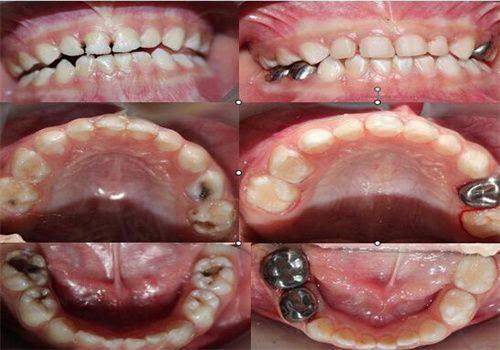

全瓷冠是一种生物相容性强且美观的牙齿修复材料,专门设计用于成年人的口腔修复。与乳牙预成冠相比,全瓷冠具有更好的美观性,通常用于修复那些缺损重度的牙齿。全瓷冠采用高强度陶瓷制成,外观上不仅与自然牙齿相似,还能满足成人对外观的高要求。

成年人口腔中的多种复杂因素使得全瓷冠成为一个热门的修复选择。由于全瓷冠不含金属成分,它的制作过程包括了现代高端的美学设计,因此它在视觉上更为自然美观,修复后几乎无法察觉。

此外,全瓷冠同样能够承担重力和压力,这使它们在受力方面相对更为坚固。然而,因其材料特性的不同,成年人的全瓷冠可能在价格上较高,通常需要数千元。这种情况下,患者可以和医生进行充分沟通,选择至佳的治疗方案。

选择合适的牙齿修复方式是患者在接受牙科治疗中需要重点关注的问题。对于儿童来说,乳牙预成冠通常是避免龋齿扩展和维持牙齿生长的重要方法;对于成年人,选择全瓷冠则需要根据牙齿缺损的具体情况进行综合考虑。

对于成人来说,选择全瓷冠的决策则更复杂,患者应考虑牙齿的现有状况、所需修复的面积及对美观的要求。在此过程中,患者的治疗经验和医生的建议是决定治疗方案的关键。

在成人方面,某位35岁的成年患者因用力过猛而导致一颗后牙崩裂,经过评估后决定进行全瓷冠修复。治疗完成后,患者十分满意,且在进行日常咀嚼时没有出现任何不适。两例皆说明了根据牙齿的具体情况选择修复方法的重要性。